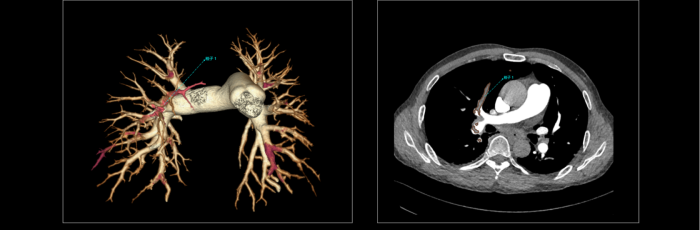

联影智能CT肺栓塞智能分析系统能够提供PE分诊预警、栓子检出和量化、肺血管智能分割和重建等功能,帮助医生及时诊断PE,鉴别诊断急性胸痛患者。同时,肺栓塞智能分析系统能够自动、准确地进行心室测量和肺动脉测量,提示右心室增宽和肺动脉增宽等PE相关风险征象,为早期PE检测和风险分层提供参考,辅助医生制定更优的诊疗方案,改善预后。

联影智能CT肺栓塞人工智能可一键智能分割、重建完整肺血管和栓子,360°展示肺动脉走行和栓子分布位置;高灵敏检出和定位栓子,提供量化分析,并自动计算RV/LV和PA/Ao,全面辅助诊疗,为PE的早期识别和临床风险分层提供强有力的智能工具;而快速分诊预警更是能够助力危急患者尽早进入诊疗环节。此外,AI可智能生成文本报告和归档图像,支持一键胶片打印。通过对救治全流程的加速优化,AI能够辅助医生快速识别隐匿肺栓塞,让胸痛患者跑赢生死竞速。